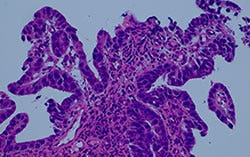

Figure 4: Comparison of a halogen lamp with filter versus a generic LED and a True Color LED

Olympus’ commitment to innovation produced the True Color LED (patent pending), which provides the color rendering and luminosity performance that pathologists are accustomed to with the halogen lamp and filter method. The high-quality illumination of this new light source is not achievable with commercially-available bright LEDs. The BX53 microscope equipped with this white LED light source is advantageous for transmission brightfield microscopy as well as other observation methods. Its brightness level is intense enough to be used in multiheaded discussion and teaching systems for simultaneous observation, and its high color rendering white LED provides the color integrity performance that pathologists require for reliable specimen observation.